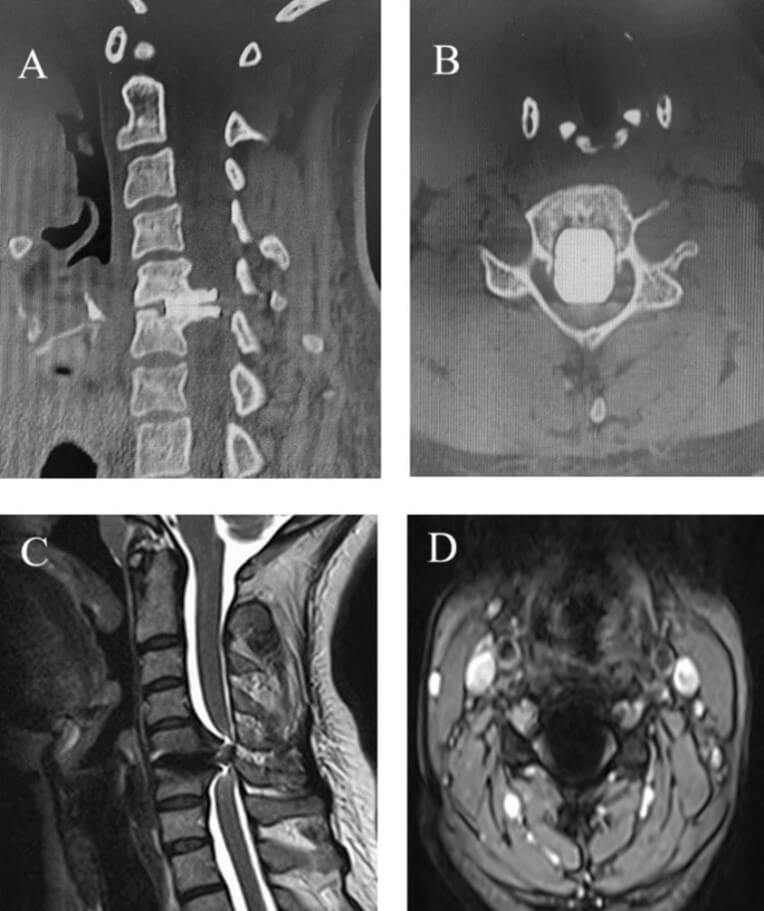

On physical examination, the patient exhibited muscle strength graded 4/5 in the right upper and lower extremities, ataxic gait, a positive Hoffman’s sign on the right, and hyperactive deep tendon reflexes in all extremities. Imaging studies with cervical CT and MRI revealed a migrated cervical prosthesis occupying more than half of the spinal canal, causing spinal cord compression (Figure 1).

A) Sagittal and B) axial CT images, C) sagittal T2 and D) axial T2 MR images. The migrated cervical prosthesis occupies more than half of the spinal canal and compresses the spinal cord. MR images are suboptimal due to metal artifact.